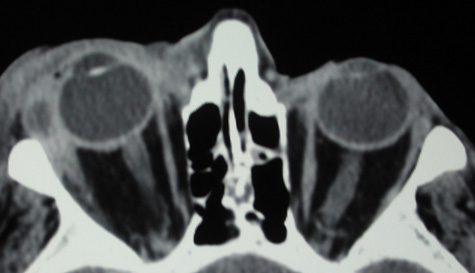

Routine skull films and polytomography have been supplanted by CT in the evaluation of patients with orbital cellulitis.57 CT allows the clinician to differentiate a preseptal cellulitis from an orbital cellulitis.58 If orbital cellulitis has resulted from adjacent intercurrent sinus infection, the diagnosis can be made and the extent of the sinus disease estimated. Sinuses may show changes of osteomyelitis with blurring of the osseous margins of the sinuses, air–fluid levels, or inflammatory tissue within the normally aerated sinus.59 Central nervous system complications can be assessed by neuroimaging, and progression of disease can also be monitored.58

CT should be performed using thin-section (2–4 mm) high-resolution scanning with multiple views of both bone and soft tissue detail.53 Axial and coronal views should be obtained; in one-third of patients with subperiosteal abscesses, the abscess was seen in the coronal sections only.18 Helical CT is a fairly new technology that allows increased resolution with decreased imaging time.60 This type of scan may be especially beneficial in children because of the ability to obtain good imaging with a shorter imaging time.60 elica He HhIntravenous contrast material is not advocated at all centers because there is intrinsically high contrast between infectious changes and orbital fat. However, some authors believe that it is essential to the diagnosis, and it thus remains the preference of the individual clinician, as well as the neuroradiologist.22,59,62

With preseptal inflammation, CT demonstrates soft tissue swelling of the eyelids and tissue adjacent to the orbital septum (Fig. 15). The orbit is not involved, and usually the sinuses do not show evidence of inflammation. The distinction between inflammatory preseptal cellulitis and edema cannot be made.63

Fig. 15. Computed tomography showing preseptal cellulitis of left eye. Note that all swelling is anterior to the orbital septum.